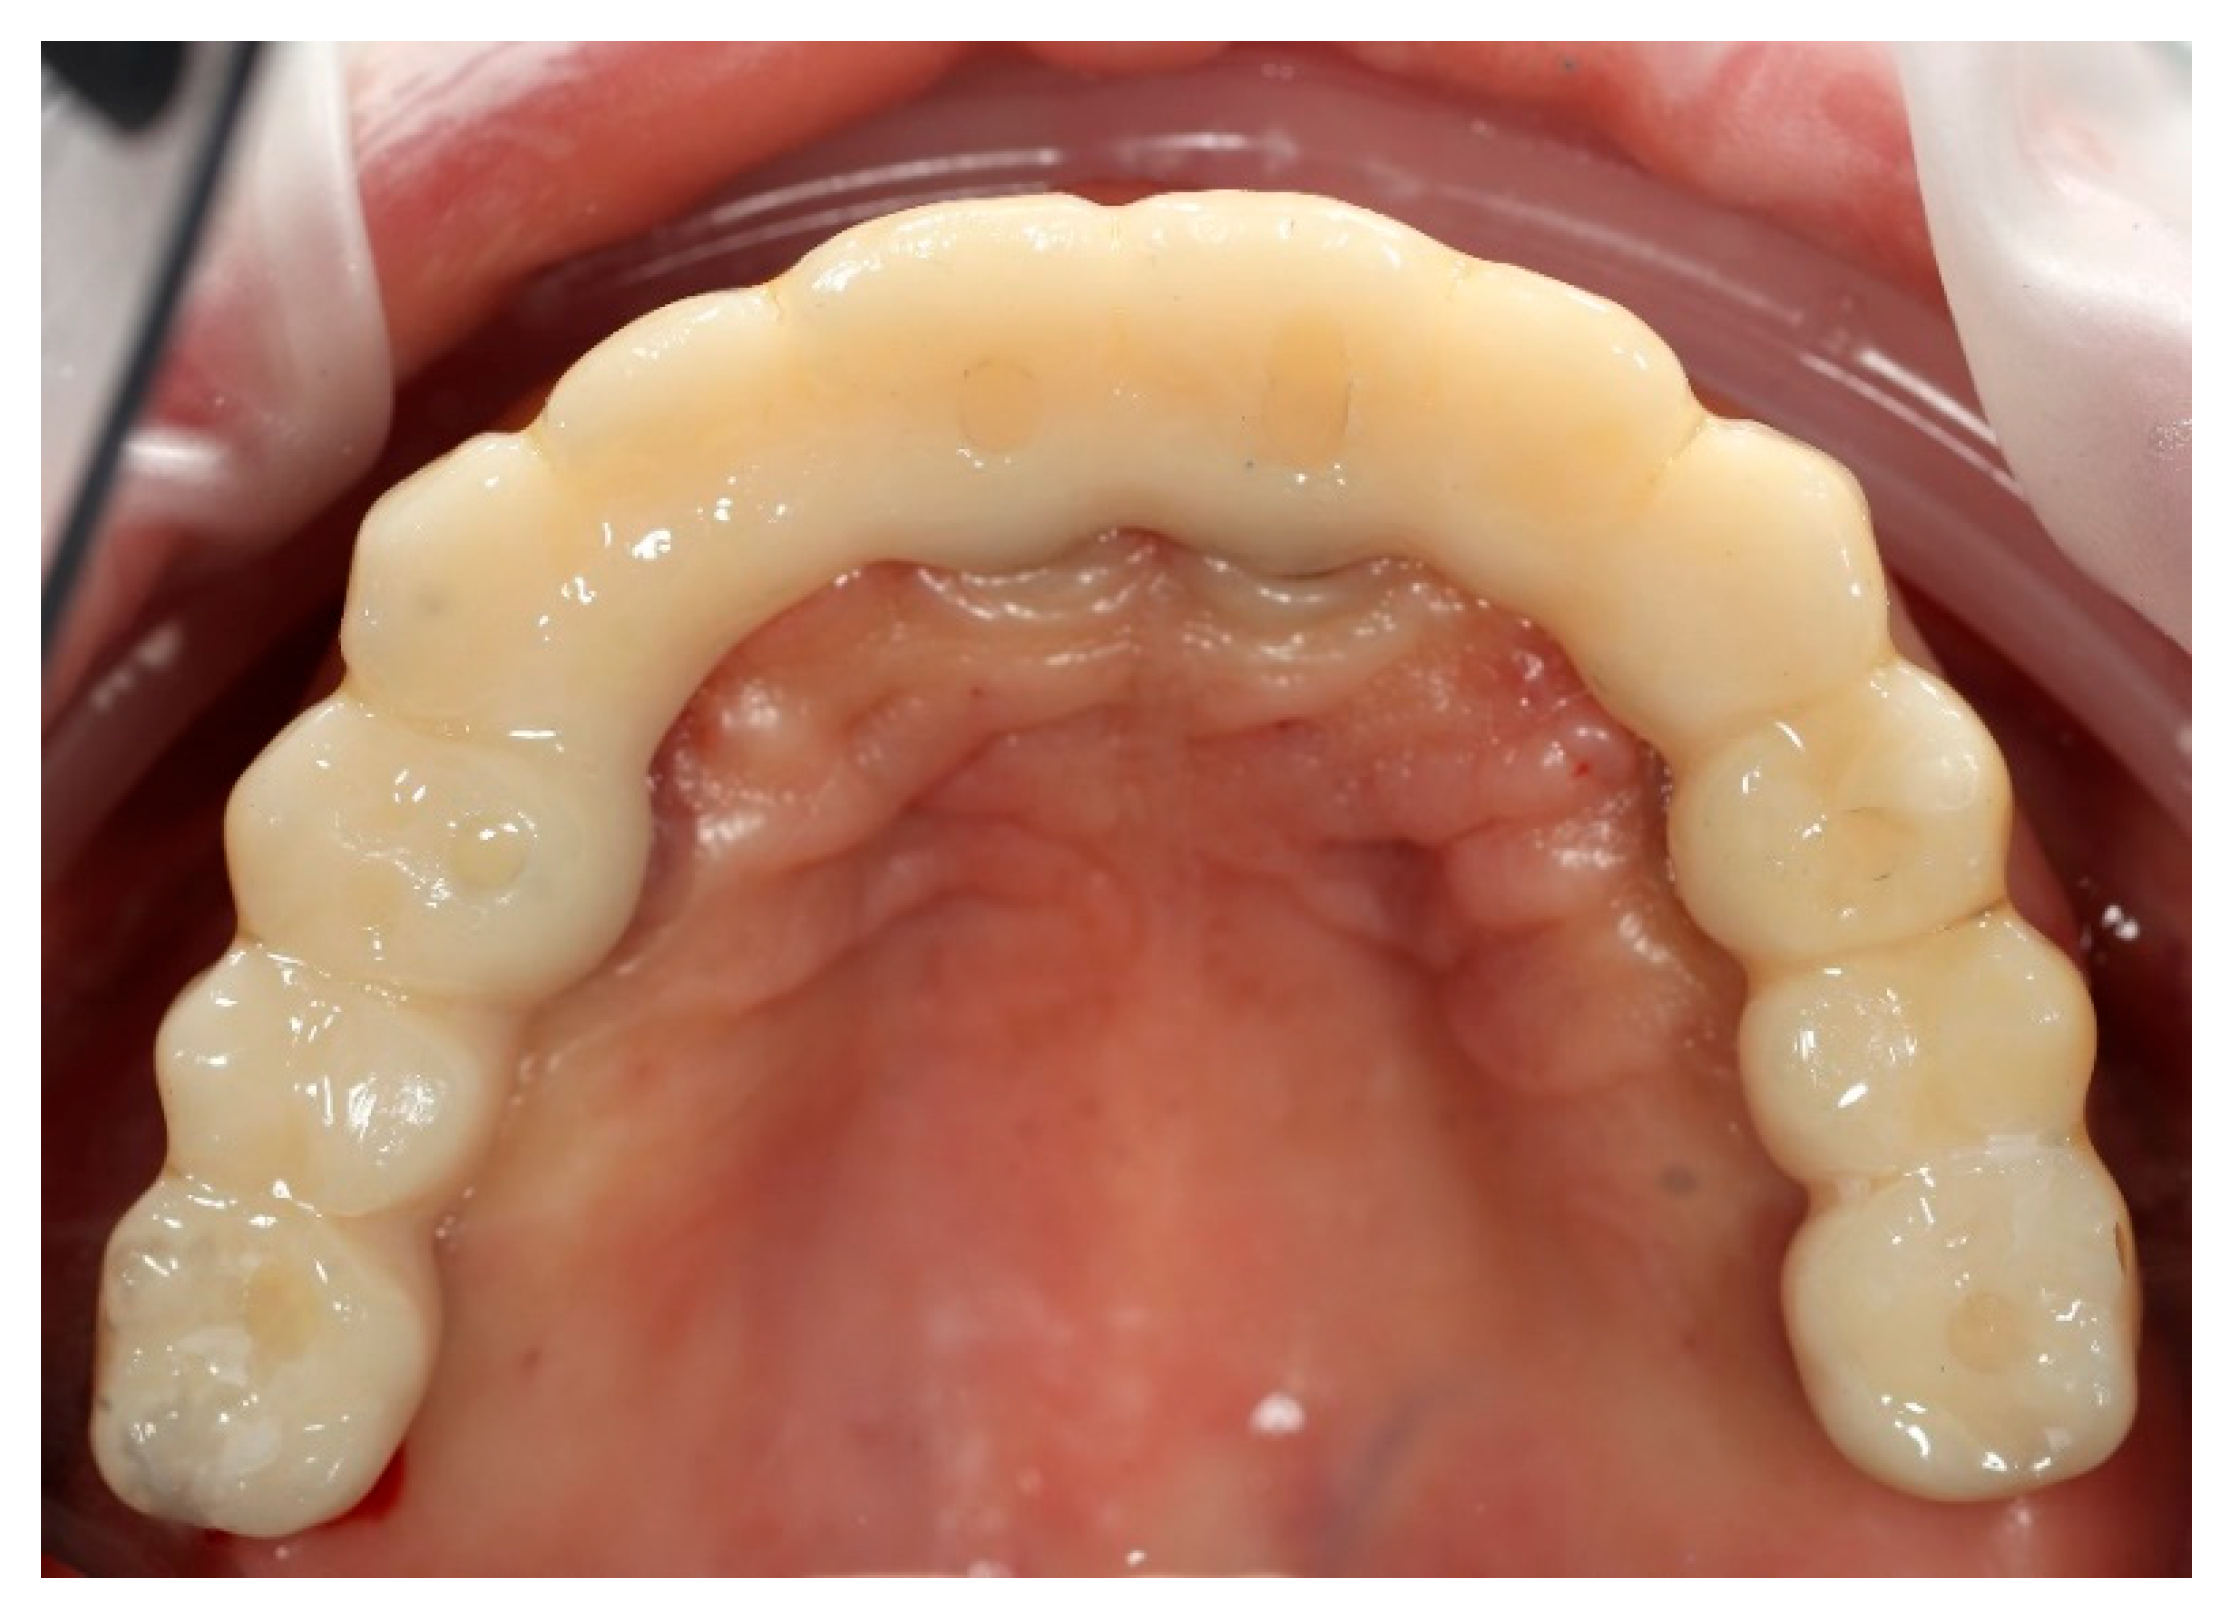

Upon removal of the provisional bridge from the multi-unit abutments, well-conditioned soft tissues were observed, adequately shaped by ovate pontics and corresponding to the requirements of the FP1-type full-arch prosthesis (Figure 13). No signs of inflammation or adverse response were noticed. As highlighted in the literature, provisional restorations are considered crucial for conditioning peri-implant soft tissues, as they help to establish the emergence profile and papillae prior to the definitive prosthesis being fitted [20].

Figure 13. Multi-unit abutments in situ after the removal of the provisional bridge, showing well-healed peri-implant soft tissues contoured by the pontics of the temporary restoration.